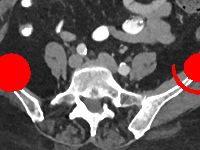

Visual comparison. As shown in Fig. 5, metallic implants such as spinal rods and hip prosthesis cause severe streaky artifacts and metal shadows, which obscure bone structures around them. cGan-CT cannot recover image intensity correctly for both cases. Sinogram domain or dual-domain methods perform much better than cGan-CT. LI, NMAR, and CNNMAR introduce strong secondary artifacts and distort the whole images. In NMAR images, there are fake bone structures around the metals, which is related to segmentation error in the prior image from strong metal artifacts. The segmentation error is also visible in NMAR sinogram. CNNMAR cannot restore the correct bone structures between rods in case 1. The tissues around the metals are over-smoothed in DuDoNet because LI sinogram and image are used as inputs, and the missing information cannot be inferred later. Our model retains more structural information than DuDoNet and generates anatomically more faithful artifact-reduced images.

Visual comparison. Fig. 7 shows two clinical CT images with metal artifacts. Case 1 is with moderate metal artifacts. cGan-CT does not suppress the artifacts completely and generates some fake details. LI, NMAR, CNN-MAR remove all the artifacts but introduce new streak artifacts, which is caused by the discontinuity in the corrected sinogram. DuDoNet outputs over-smoothed sinogram, which leads to blurred tissues close to the metal implants, such as muscle and bone. Only our model can provide realistic enhanced sinogram and remove the artifacts while retaining the structure of nearby tissues. Case 2 is very challenging as the rods bring strong metal shadows and bright artifacts around the vertebra. cGan-CT recovers the shape of vertebra but changes the overall image intensity. Other sinogram inpainting methods fail as the soft tissue and bone near the rods are heavily distorted. Our model removes part of the dark bands and reproduces correct anatomical structures around the rods.